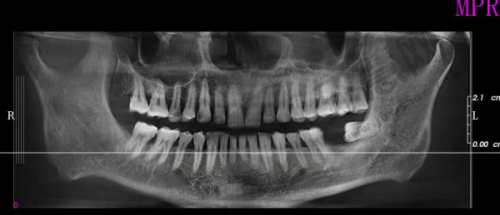

南宁同步口腔穿颧骨种植术 74200 元起项目专为上颌骨重度吸收患者定制。正常情况下,上颌骨骨量重度不足时传统种植牙手术难以进行,而穿颧骨种植术突破了这一限制。手术通过将种植体植入颧骨,利用颧骨骨量支撑种植体实现牙齿种植。南宁同步口腔开展此手术会采用精良设备和技术,确保精细性和安心性。术前,医生会对患者进行全方面口腔检查,包括口腔 CT 等,了解口腔状况和骨骼结构,制定个性化治疗方案。手术中,医生凭借丰富经验和不错技术将种植体正确植入颧骨。术后,医院提供专精护理指导帮助患者修复。74200 元起的收费包含手术费、种植体费用等,但具体价格会因种植体品牌、手术复杂程度等因素不同。